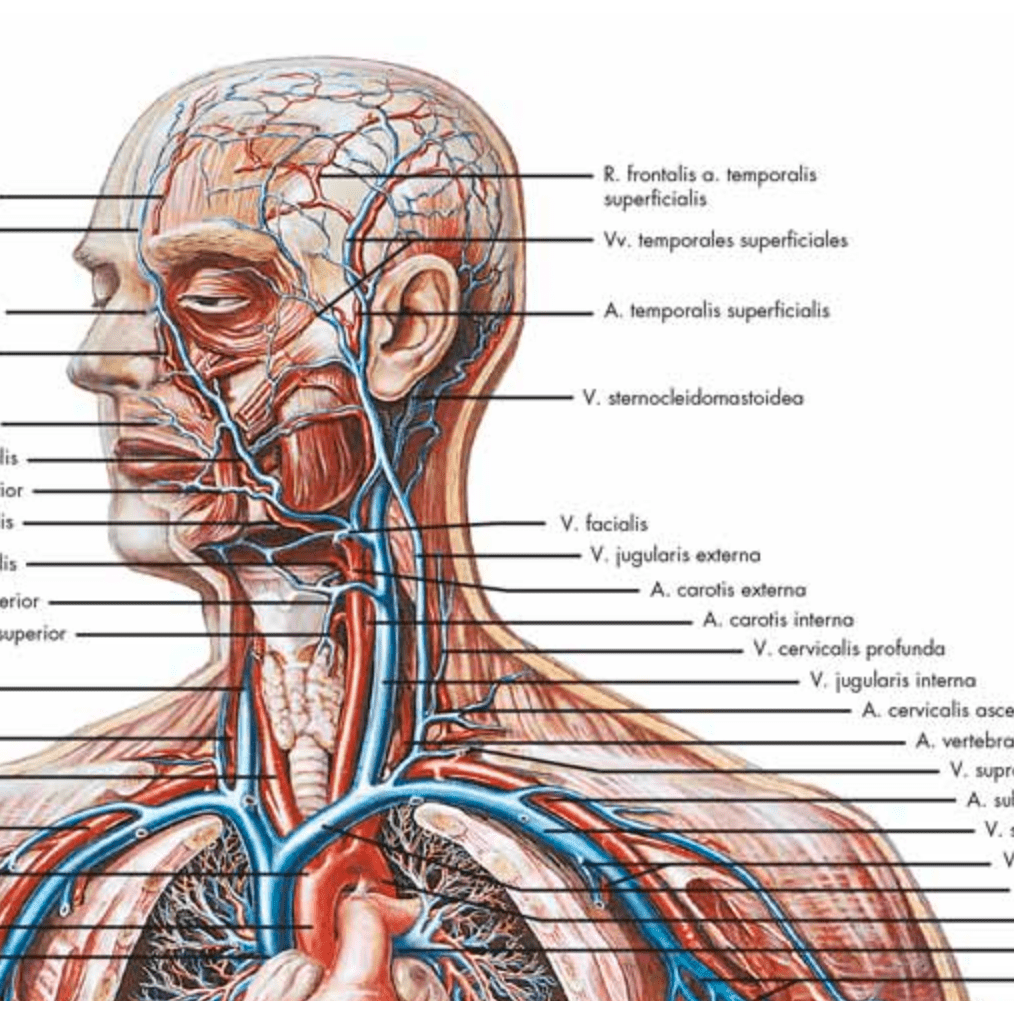

Muscle posters

Muscles provide movement to the musculoskeletal system, and their origins, insertions and lodges are clinically important for every healthcare professional. That is why we at eAnatomi have both developed and designed our own anatomy posters, which provide the ultimate overview of all the muscles of the body. On this page you can find both our own posters and posters from other manufacturers. We offer posters in several different languages such as pure Latin, Danish, English and Swedish, etc.